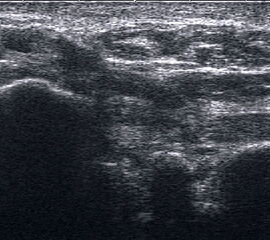

Längsschnitt über dem Lig. fibulocalcaneare. Die Peronealsehnen erscheinen als echoreiche runde bis ovaläre Struktur.

Abbildung 19

Lagerung: Rückenlage, OSG in Neutralstellung.

Schnittebene: LS über Lig. fibulocalcaneare.

Referenzstrukturen: Fibulaspitze und Talus.

Befunde: Das Lig. fibulocalcaneare is nativ schlecht abgrenzbar, da es in die Tiefe und nicht parallel zum Schallkopf verläuft. Direkt über das Band ziehen quer getroffen die Peronäussehnen. Durch die Distorsion kann auch das Peritendineum peroneale einreißen. Die Peronealsehnen sind dann in ihrer Sehnenscheide von Blut umgeben, was sich als echoarmer Ring (Halo-Phänomen) darstellt und ein indirektes Zeichen für eine Verletzung des Lig. fibulocalcaneare ist.